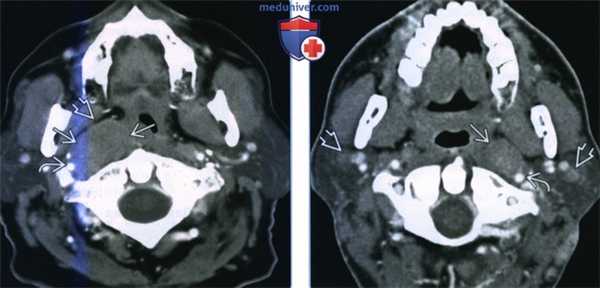

(Слева) КТ с КУ, аксиальная проекция. Пациент с неходжкинской лимфомой. В заглоточном пространстве, медиальнее правой внутренней сонной артерии определяется крупное новообразование, равномерно накапливающее контрастное вещество. Жировая клетчатка окологлоточного пространства смещена вперед и в латеральную сторону.

(Справа) КТ с КУ, аксиальная проекция, другой пациент с неходжкинской лимфомой. В левой части заглоточного пространства имеется крупный гомогенный лимфоузел овальной формы без признаков некроза. Левая внутренняя сонная артерия смещена назад и в латеральную сторону. Околоушные лимфоузлы также несколько увеличены.